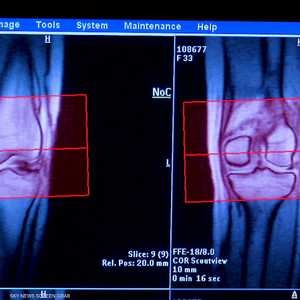

ويلفت الدكتور قريشي إلى أن الصدفية اللويحية هي الأكثر انتشارا، وهي عبارة عن ظهور طبقات سميكة حمراء على الأكواع والركب وجدع الجسم.

وهناك أيضا الصدفية القطرية أو النقطية بعد الإصابة بالتهاب بكثيري في اللوزتين، وصدفية الرأس يصاحبها احمرار وقشور سميكة مزعجة، وصدفية ثنايات الجلد مثل أسفل الثدي والإبط والعانة. وعادة ما تسبب الحكة والتعرق الصدفية البثرية أكثر عند المدخنين في راحة اليد وكعب القدم على شكل تجمع قيح تحت الجلد، وصدفية الأظافر التي تؤدي إلى ارتفاع الظفر عن الجلد أو نقاط أو حفر، وفي بعض الأحيان سماكة الظفر وميوله للإصفرار، فيما تصيب الصدفية الحمراء كامل الجسم وتحتاج إلى تدخل سريع لعلاجها، فيما تسبب صدفية المفاصل تورم وتيبس المفاصل وتؤدي إلى تدهور المفصل إذا لم يتم اكتشافها وعلاجها سريعًا.